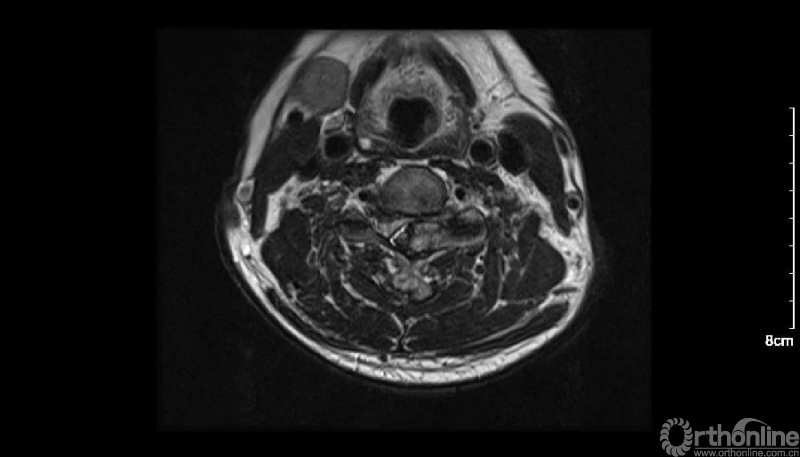

入院查体患者四肢肌张力高,双侧hoffman阳性。CT及MRI检查提示C4/5左侧关节突内缘有一巨大骨块(15mm*16mm),相应节段椎管严重狭窄。椎管内骨块的前端还有一游离骨块。

影像学资料